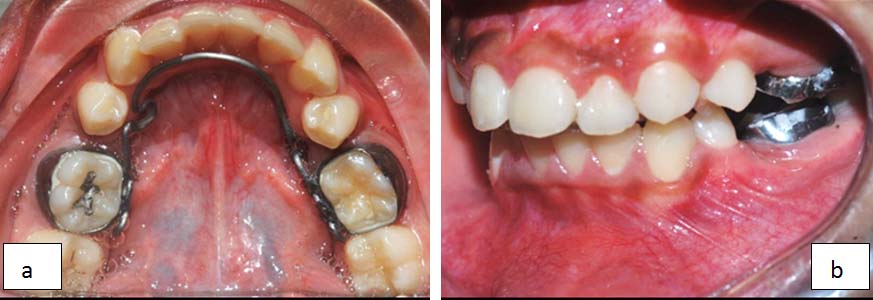

A holding arch with anterior bite plane was also given in the upper arch to attain clearance for the correction of scissor bite [Table/Fig-3].

Holding arch with anterior bite plane in the upper arch.